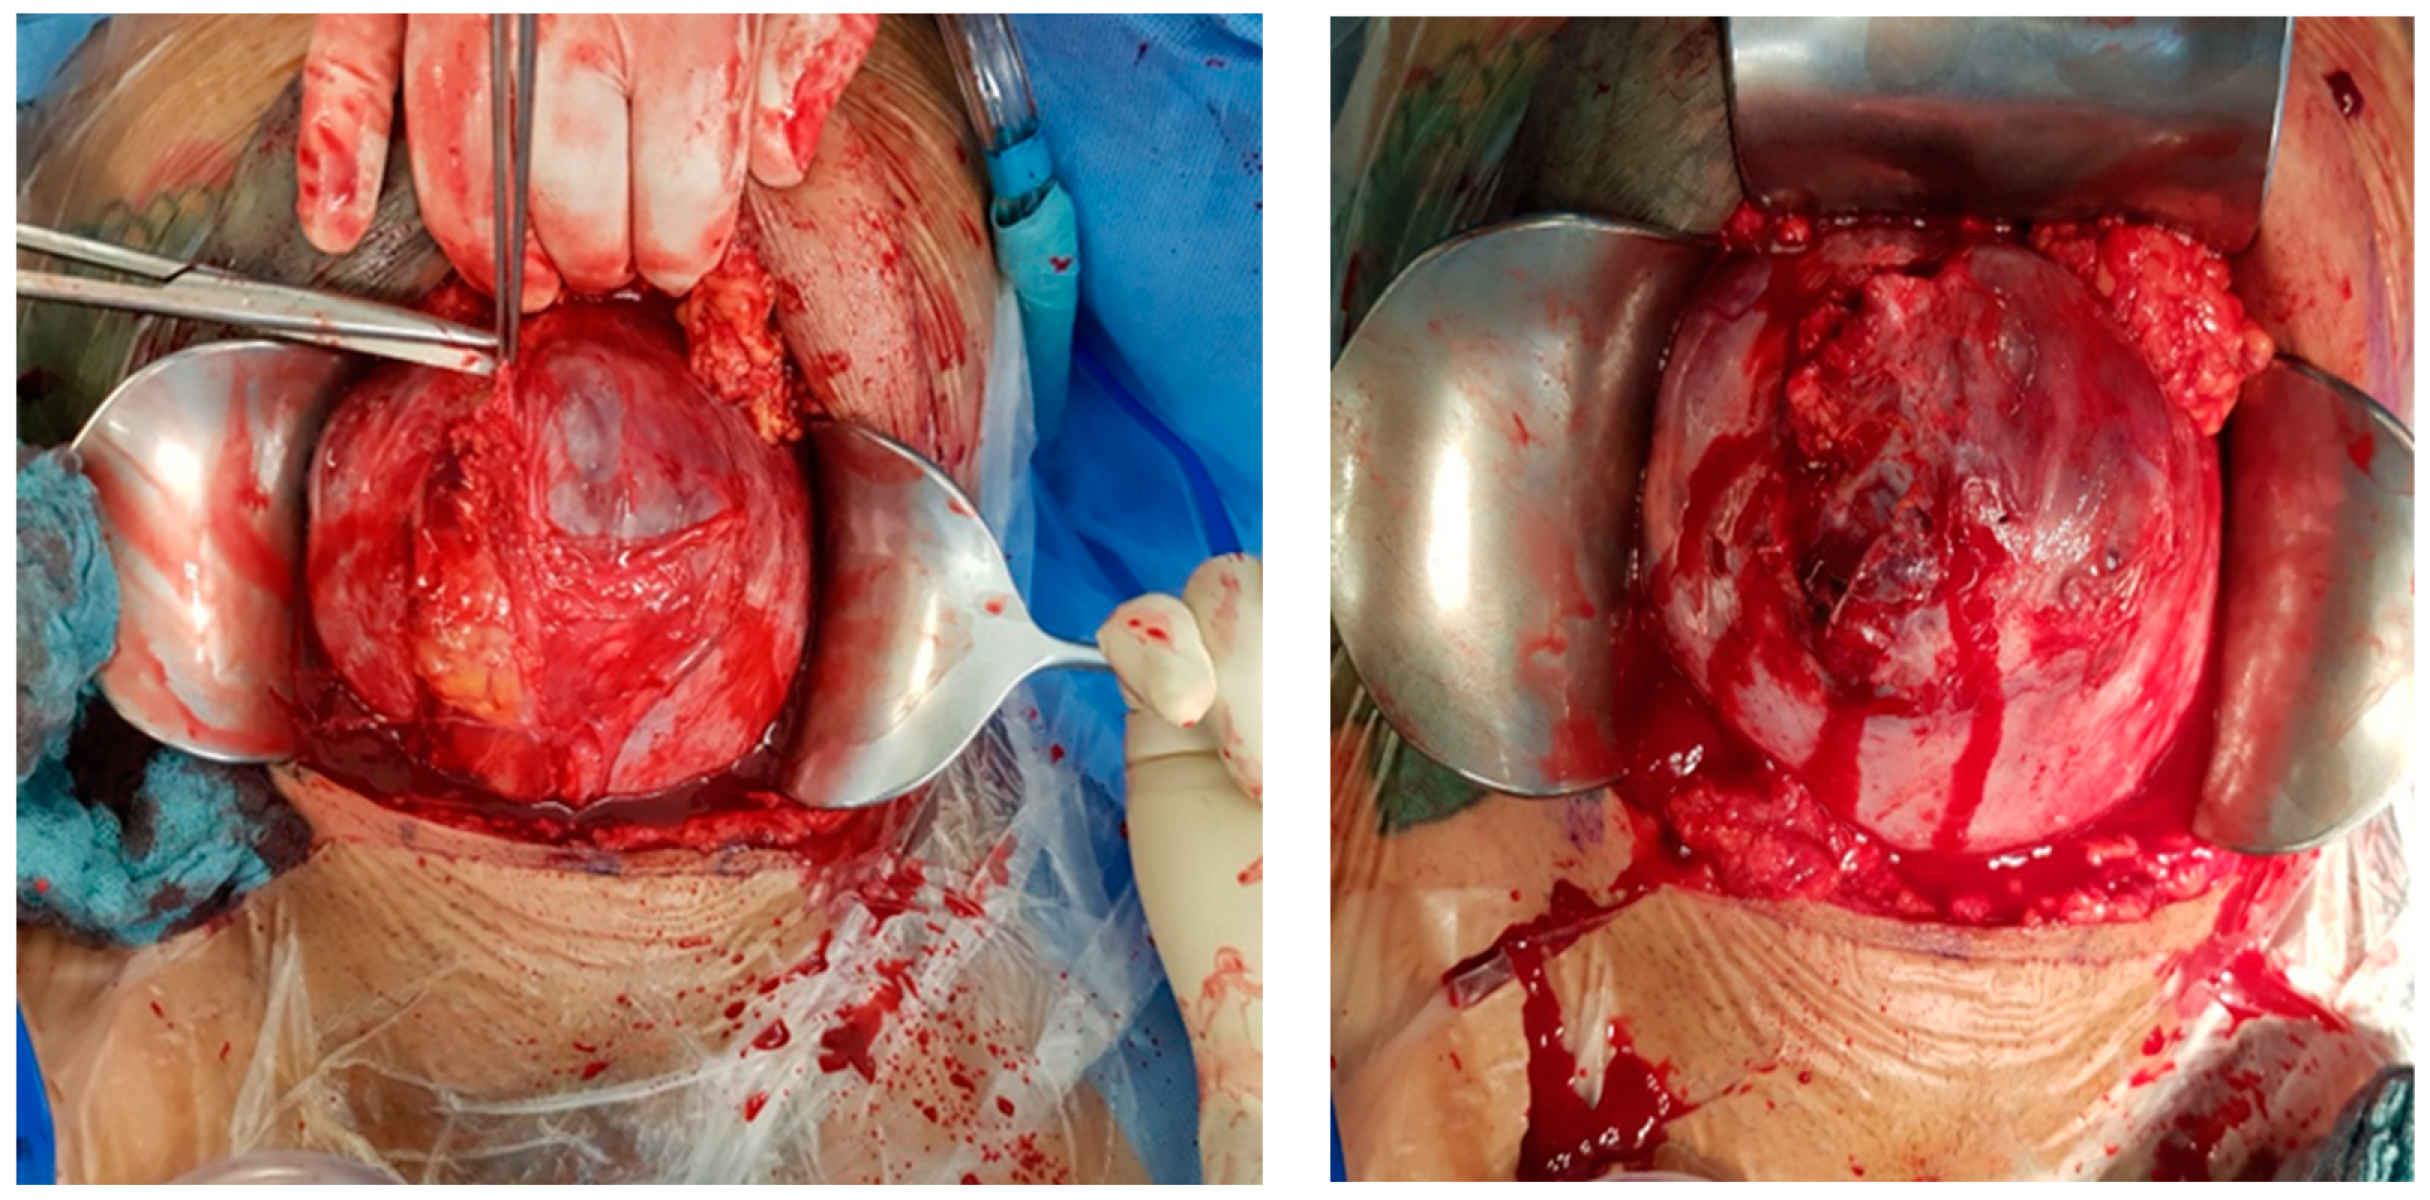

Intraoperative findings (Figure 8):

Figure 8.

Depict the uterus during and after hysterectomy performed for placenta increta.